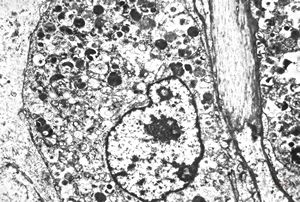

F, 24y. | molluscum contagiosum … virions

F, 24y. | molluscum contagiosum

F, 24y. | molluscum contagiosum

F, 7y. | molluscum contagiosum … virions